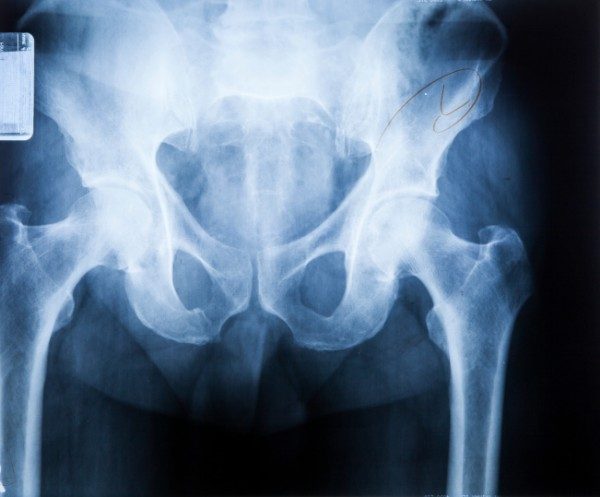

La sindrome dell’anca a scatto, nota anche come anca del ballerino è una condizione in cui si ha la sensazione di uno “scatto” quando si fa un particolare movimento, come durante una corsa, quando ci si alza da una sedia o semplicemente camminando. Spesso si sente anche un vero e proprio rumore. E’ un qualcosa di abbastanza comune che solitamente non comporta complicanze, ma chi utilizza molto tale articolazione, magari perché è un atlta, un ballerino o sta molte ore in piedi, può arrivare ad essere condizionato da debolezza e dolore che interferiscono con le prestazioni. Ecco cosa occorre sapere al riguardo.